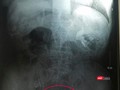

Viên sỏi bàng quang có hình dáng và kích thước tương tự như quả trứng vịt trên phim chụp X-Quang của bệnh nhân T. (ảnh BVCC)

“Giải cứu” bàng quang khỏi viên sỏi khủng bằng quả trứng vịt